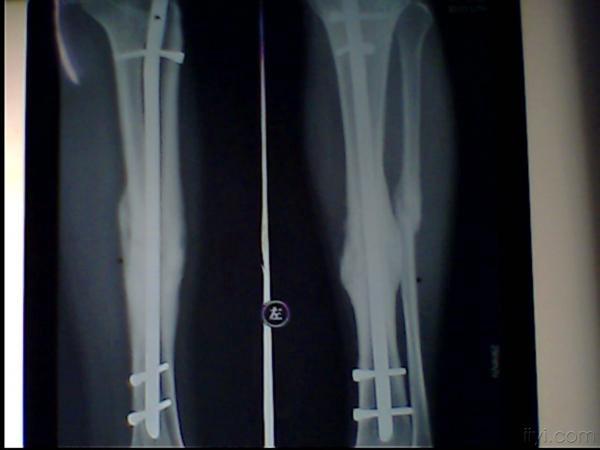

主 诉: 左胫骨骨折交锁髓内钉内固定手术后1年余

辅检:左胫骨骨折内固定术后

要求取出内固定物,如图

讨论:1、第二枚锁钉是弯了还是断了?

2、上下锁钉都没有问题,为什么中间的钉子有这样大的应力?